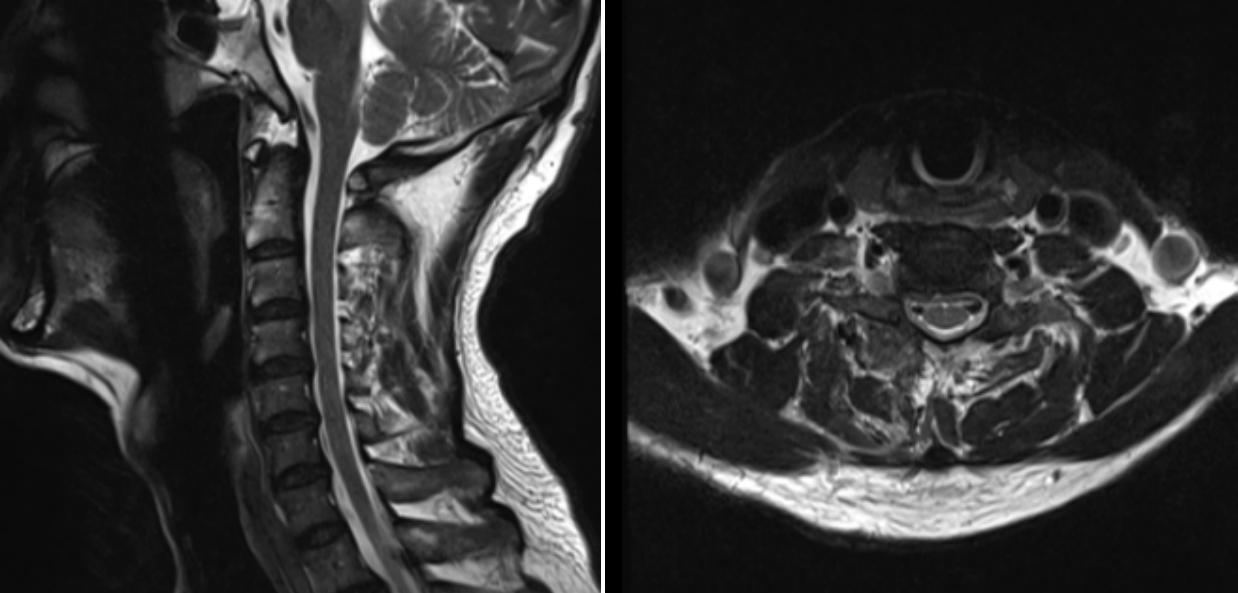

術(shù)后第一天MRI圖像

術(shù)后效果立竿見影,患者的疼痛癥狀得到了顯著緩解,麻木感也逐漸消退。術(shù)后1天,患者便能在醫(yī)護人員的指導下下床活動。經(jīng)過3天的觀察與護理,患者身體狀況良好,順利出院,手術(shù)取得圓滿成功。